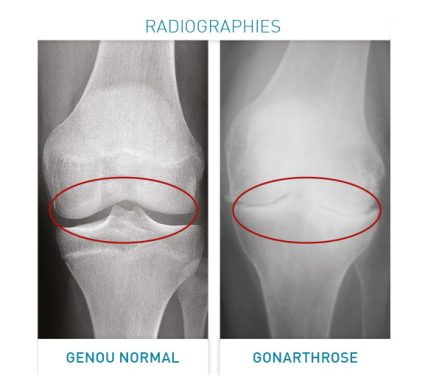

L'Arthrose et la Polyarthrite Rhumatoïde sont les maladies articulaires très douloureuses causées par une usure précoce du cartilage des articulations. Elle peut survenir à tout âge et augmenter avec l'âge.

Les conséquences graves de ces deux maladies : elles se manifestent par des douleurs récurrents des articulations, des poussées inflammatoires, affaiblissement progressif des muscles autour de l'articulation , une difficulté à effectuer certains mouvements articulaires, gène fonctionnelle, mobilité réduite de l'articulation , sensibilité de l'articulation, invalidation et entraîner les chutes et perte d'autonomie. C'est un vrai handicap.

Les articulations sont sollicitées et le cartilage s'use progressivement. Le cartilage disparaît pour laisser l'os à nu. Elles peuvent toucher la colonne vertébrale et les articulations les plus atteintes sont celles : des mains, des poignets, des hanches, des genoux et des pieds.

- Réduire l'inflammation de ces maladies, la douleur dans les genoux, les tendons, les muscles de la dégénérescence des articulations.

- Ralentir la détérioration du cartilage.

- Stimuler la formation de masse osseuse et augmenter l'épaisseur de la masse osseuse.

- Nourrir et réduire la dégénérescence articulaire.